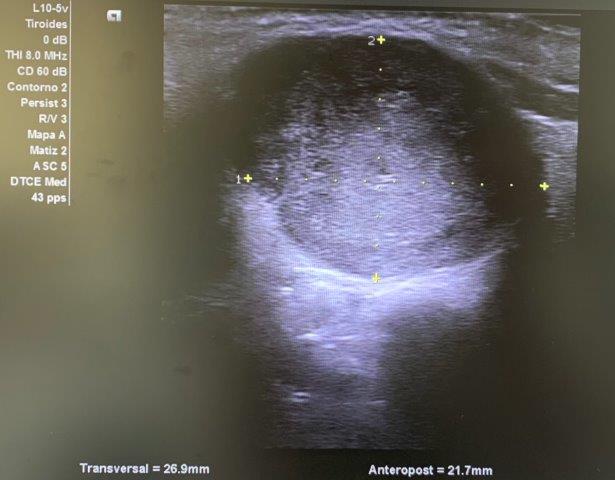

ECO POCUS: imagen isoecoica, heterogénea, redondeada con captación periférica de Doppler, que mide 26.9 x 21.7 mm (corte transversal) y 30.3 mm (corte longitudinal). Vemos un bultoma originado en la cola de glándula parótida.